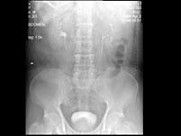

- 多项选择题男,67岁, 无痛性血尿1月,IVP和MRI检查如图示, 下列说法正确的是 ( )

A、IVP示左侧中组肾盏未见显影

B、左肾中部内侧可见类圆形不均匀信号肿块突向外

C、左肾上极可见一T

WI为高信号圆形病灶,边界清楚D、左肾中部病灶考虑为小肾癌

E、左肾上极病灶考虑为肾囊肿